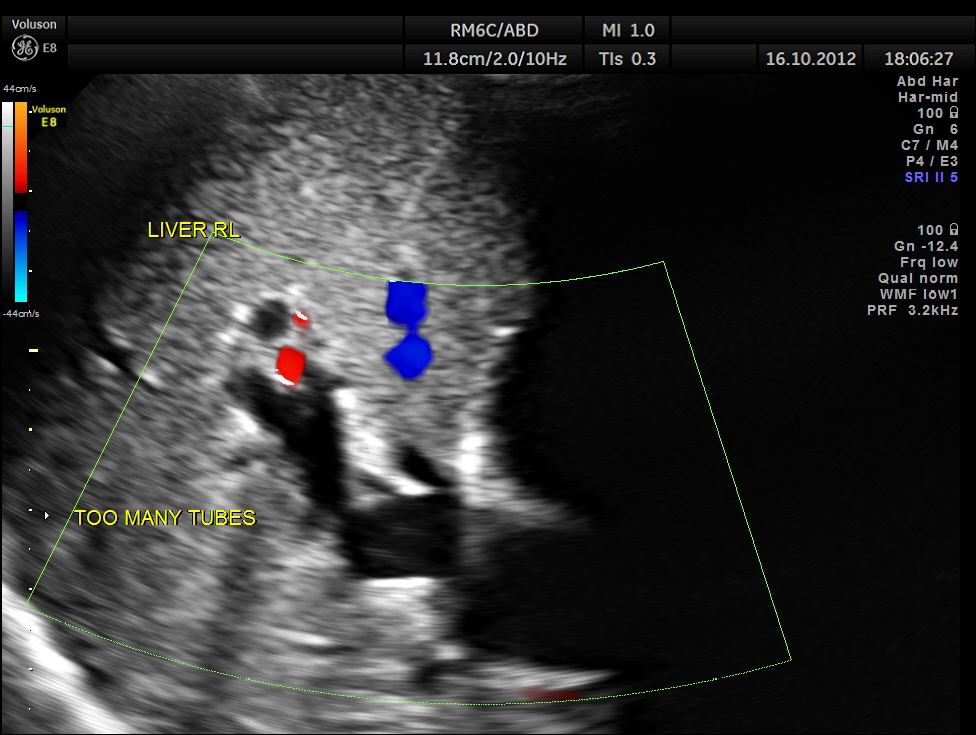

Courvoisier’s law (or Courvoisier syndrome, or Courvoisier’s sign or Courvoisier-Terrier’s sign) states that in the presence of an enlarged gallbladder which is nontender and accompanied with mild jaundice, the cause is unlikely to be gallstones. Usually, the term is used to describe the physical examination finding of the right-upper quadrant of the abdomen. This sign implicated possible malignancy of the gall bladder or pancreas and the swelling is unlikely due to gallstones.

This was a 55 year old man with history of jaundice and upper abdominal pain .